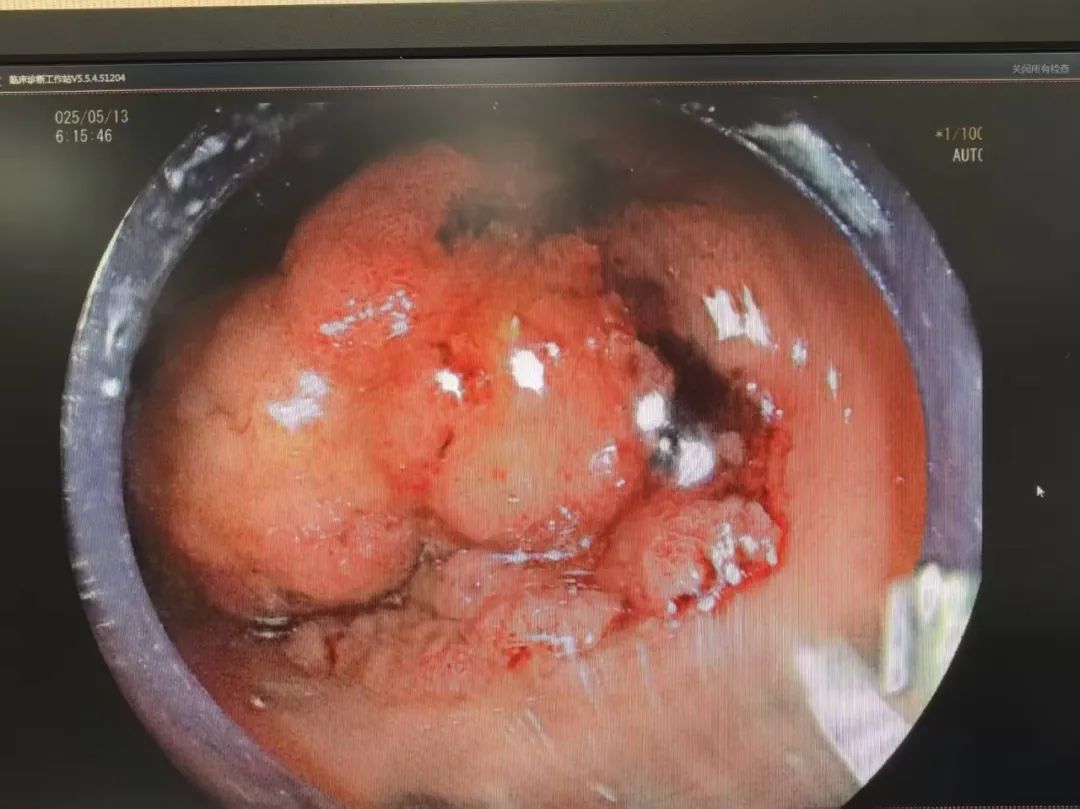

直肠菜花状肿物

术后标本切开,见菜花样肿瘤.

镜检查发现直肠肿物,直肠指诊2点钟方向距肛缘3cm处触及菜花样肿物